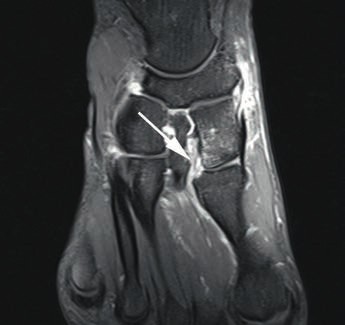

- Die Grad-I-Verletzung umschreibt eine Distorsion des Lisfranc-Bandes ohne mechanische Instabilität. Pa tienten mit dieser Verletzung klagen über Schmerzen in der Region des dorsalen Lisfranc’schen Bandes. Die Röntgenaufnahmen unter Belastung zeigen einen unauffälligen Befund. Kernspintomografisch lässt sich eine Signaländerung im Lisfranc-Bandkomplex nachweisen (siehe Abb. 2), jedoch keine Kontinuitätsunterbrechnung. Im 3‑Phasen-Skelettszintigramm zeigt sich eine Mehranreicherung 19 20.

Die dorsalen und plantaren Anteile des Lisfranc-Bandkomplexes lassen sich kernspintomografisch gut und präzise darstellen (Abb. 6) 28. Wichtig für die Praxis erscheint in diesem Zusammenhang die enge Zusammenarbeit zwischen Radiologen und Orthopäden, denn nur eine akkurate und symptomorientierte Durchführung des Schnittbildverfahrens ermöglicht die entsprechende Darstellung der Bandverletzung mit der gewünschten diagnostischen Sicherheit 29. Bei einer Standardabbildung des Vorfußes im MRT werden die Lisfranc-Bänder oft nicht exakt dargestellt, was eine Aussage zum Ausmaß der Verletzung problematisch macht. Zur exakten Darstellung von knöchernen Verletzungen bietet das Computertomogramm die beste Aufiösung 30.

Bei Athleten tritt eine Verletzung des Lisfranc-Bandkomplexes typischerweise auf, wenn der Fuß bei gleichzeitiger Plantarflexion und leichter Rotation axial belast et wird 43 44. Die Zerreißung des Lisfranc-Bandkomplexes führt zu einer tarsometatarsalen Dehiszenz mit Dislokation der Metatarsale-II-Basis nach dorsal 45. Nunley und Vertullo (2002) 46 gehen in ihren Untersuchungen davon aus, dass es bei der Grad-I-Verletzung lediglich zu einer Distorsion des Lisfranc’schen Bandes in Verbindung mit einer Verletzung der Gelenkkapsel kommt. Aufgrund des in sich noch stabilen Kapselbandkomplexes finden sich normale Belastungsaufnahmen; die Verletzung der dorsalen Bandanteile lässt sich jedoch kernspintomografisch nachweisen 47. Bei der Grad-II-Verletzung kommt es zusätzlich zu einer vollständigen Zerreißung der dorsalen Bandanteile. Radiologisch zeigt sich dies durch das Auseinanderweichen von Os metatarsale I und II auf den Röntgenaufnahmen unter Belastung. Da die plantaren Kapselbandanteile intakt bleiben, kommt es jedoch zu keinem Absinken des Längsgewölbes in der Seitenaufnahme. Bei Grad-III-Verletzungen liegt eine komplette Zerreißung der dorsalen und plantaren Kapselbandstrukturen mit einem instabilen ersten Tarsometatarsalgelenk vor. Dies zeigt sich radiologisch durch ein Absinken des Längsgewölbes 48.